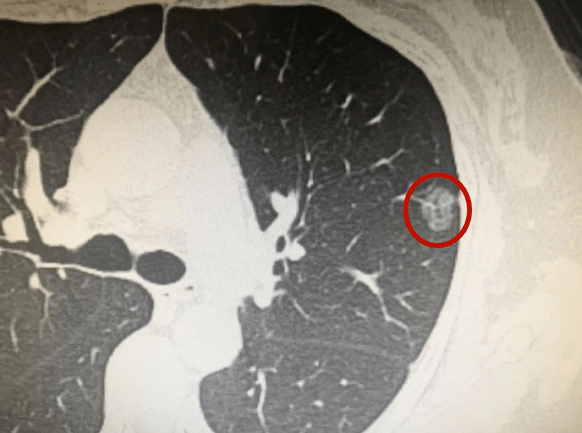

磨玻璃结节一般是由于肺部感染或者先天性结节导致的且大多数是良性的,极少数是恶性肿瘤。如果结节很大,达到一厘米、两厘米甚至三厘米,则恶性概率较高。一般上叶结节的恶性概率高于下叶结节,如果结节有毛刺,则恶性概率高于无毛刺结节;如果是纯磨玻璃结节,恶性概率低于某些实性磨玻璃结节。

因此,如果结节中有一些固体成分,要高度警惕恶性转化。如果是长期吸烟或有肺癌家族史的人群,或有肺外其他部位肿瘤史的人群,同一肺结节或毛玻璃结节的恶性转化概率和恶性风险高于其他人群。